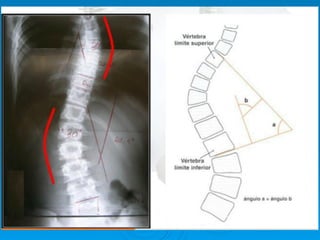

Método de Cobb: para medición del

grado de curva de la escoliosis

Ø    Se traza una línea paralela a la

superficie de los cuerpos de los

extremos de las curvas y luego

una línea perpendicular a la

línea ya trazada: el ángulo que

se forma con estas dos líneas

perpendiculares es el ángulo

que representa la magnitud en

grados de la desviación de la

columna. Las vértebras de los

extremos de la curva son los

últimos que miran hacia la

concavidad de ella.

Método de Cobb:para medición del grado de curva de la escoliosis Ø  Se traza una línea paralela a la superficie de los cuerpos de los extremos de las curvas y luego una línea perpendicular a la línea ya trazada: el ángulo que se forma con estas dos líneas perpendiculares es el ángulo que representa la magnitud en grados de la desviación de la columna. Las vértebras de los extremos de la curva son los últimos que miran hacia la concavidad de ella.